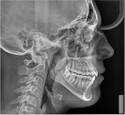

Центр проводит трёхмерное рентгенографическое исследование зубов (3D-снимок зубов), челюстей, околоносовых пазух, черепа и височно-нижнечелюстных суставов. Оборудование позволяет получить снимок высокой точности и определить степень повреждения, состояние костных структур и зубов, расположение корневых каналов. Снимки: ортопантомограмма, телерентгенограмма, конусно-лучевая компьютерная томография зубов, пазух, височно-нижнечелюстных суставов. Запись исследования на диск, распечатка на фотобумагу, описание врача-рентгенолога.